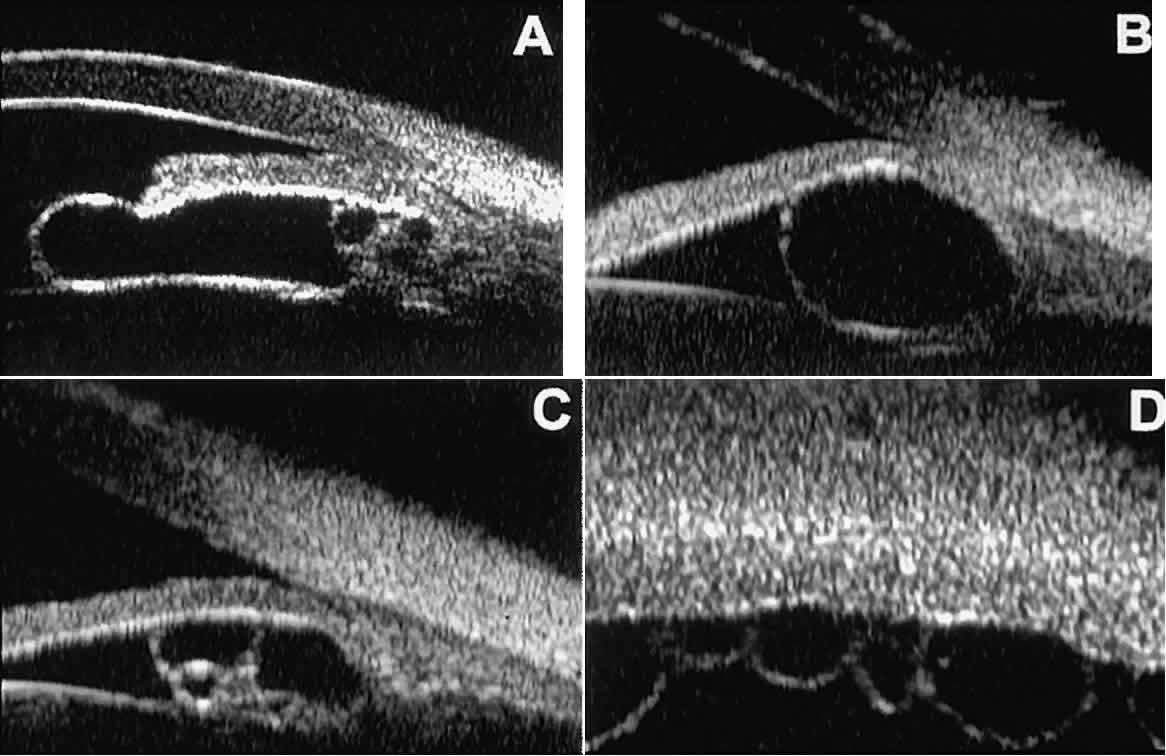

Cystic lesions of the iris and ciliary body can be of four types: primary neuroepithelial cysts, stratified squamous epithelial cysts, neuroepithelial cysts associated with solid tumors, and intratumoral cavities.15 Primary neuroepithelial cysts (see Fig. 22) are very distinct on UBM imaging. These lesions consist of a central sonolucent cavity surrounded by a thin wall of highly reflective neuroepithelial cells. They arise from the posterior surface of the iris (see Fig. 22A), in the iridociliary sulcus (see Fig. 22B and C), or from the inner aspect of the ciliary body (see Fig. 22D). They are often multifocal (see Fig. 22C and D) and bilateral.15 The largest lesions of this type typically occur in or near the horizontal meridians.

Stratified squamous epithelial cysts (Fig. 23) are almost exclusively unilateral and unifocal,15 have substantially thicker walls than do primary neuroepithelial cysts, and usually contain prominent intracavitary particles (desquamated epithelial cells). Almost all such cysts involve the peripheral iris and angle region. Such cysts are usually secondary to prior ocular surgery or laceration in which conjunctival epithelial cells were implanted into the iris stroma.

Fig. 23. UBM features of stratified squamous epithelial cysts of iris. A. Thick-walled implantation cyst of stratified squamous epithelium replacing normal iris. Note intracavitary particles. B. Bilobed stratified squamous epithelial inclusion cyst of iris with prominent intracavitary particles.

Secondary neuroepithelial cysts occur rather frequently in association with solid tumors of the iris or ciliary body.15 On UBM (Fig. 24), such cysts appear quite similar to the primary neuroepithelial cysts described above; however, they are associated with a solid mass arising within the iris or ciliary body.

Fig. 24. UBM appearance of neuroepithelial cysts associated with solid tumors of the iris and ciliary body. A. Single neuroepithelial cyst associated with iris melanoma. B. Multiple neuroepithelial cysts associated with iridociliary melanoma.